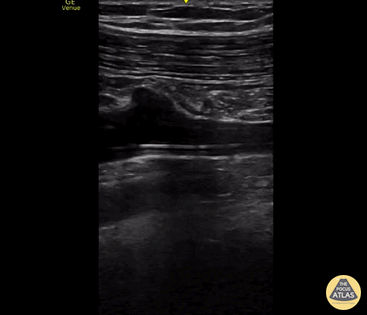

Vascular - PICC Line in Subclavian Vein

55 y/o man with septic shock and multiorgan failure due to SBP and liver failure. Picc line visualized within the R subclavian vein. longitudinal view. Alex Steinberg